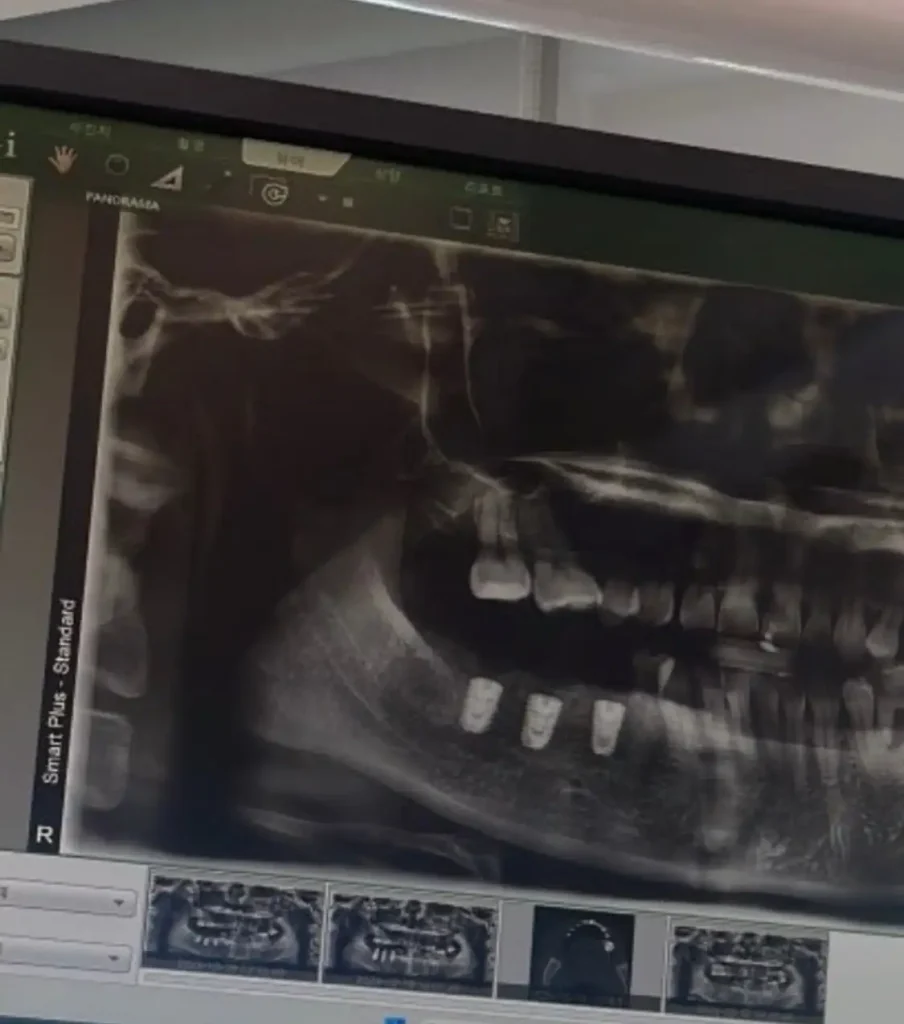

올해는 그동안의 폭토의 상흔인..어금니를 치료했다. 어금니 세개가 다 없어서 임플란트를 세개나 박았다.

비용도 비용인데 정말 처음 치료를 시작할때 부끄러웠다.

그래도 치료를 하고 나니 정말 잘했다는 생각이 드네!